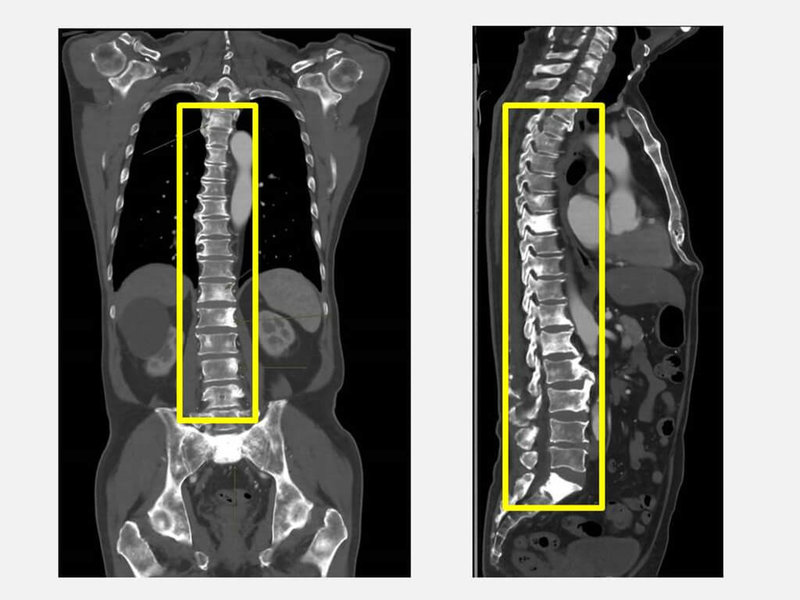

余男日前到醫院健檢時,發現攝護腺特異抗原(PSA)與鹼性磷酸酶(ALK-P)指數明顯異常,經轉介至泌尿科門診,確診為攝護腺癌合併瀰漫性骨轉移,經治療目前病情獲得控制。